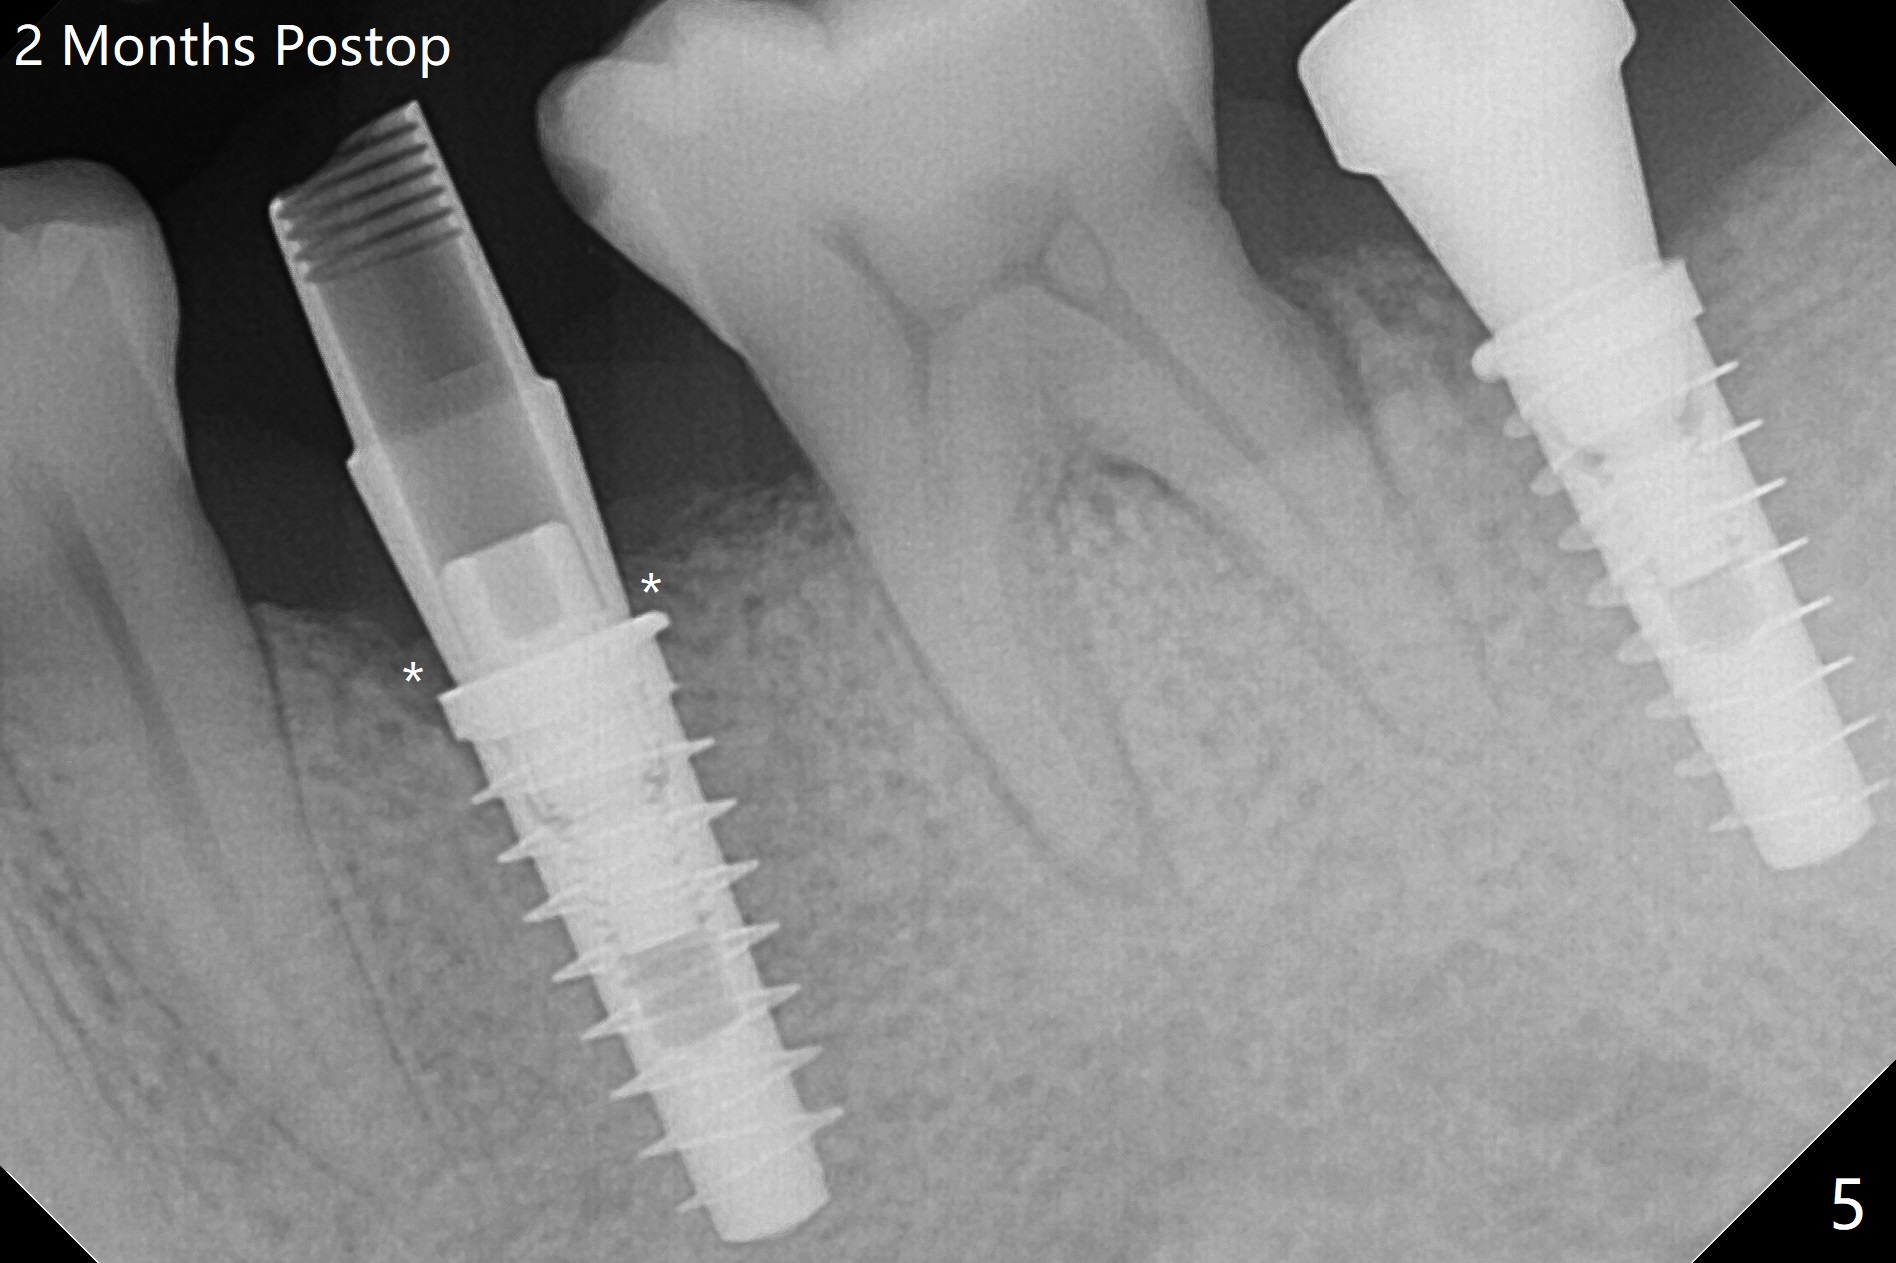

为了预防钻头遇到舌侧骨板而往颊侧偏移,有意不拔除第二前磨牙牙根。但是2.2毫米钻头钻洞很吃力,最后不得不拔除牙根,阻力骤然减少,顺利完成植入,而且颊侧间隙还够(图一,二),填入骨粉后远中螺纹间空间消失(图三箭头)。今后最后一个钻头完成钻洞后留在原位,周围放置适当量的骨粉,然后取出钻头,植入植体,这样空间可以比较全面充填。即刻种植没有颊侧偏移可能是因为设计时植体没有过多接触舌侧骨板(图四L)。第二磨牙延期种植需要切开是因为颊侧角化牙龈不足。术后两个月,前磨牙植体顶端似乎被牙槽嵴覆盖了(图五 *)。术后五个月,旋转7愈合基台,下面植体疼痛,可能与植体螺纹断裂有关(图六:>),5取模。